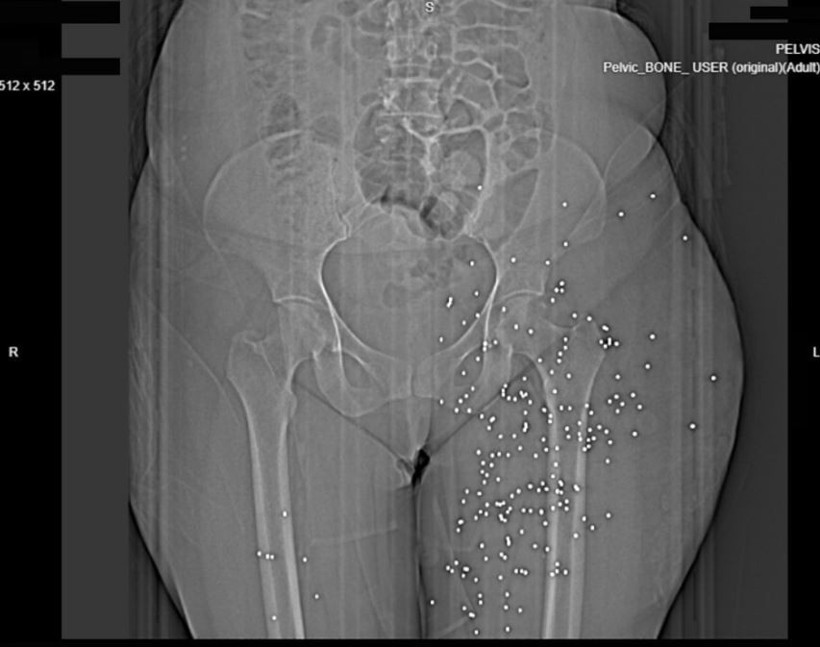

Bu görüntüler, güvenlik güçlerinin yüksek kalibreli silahlar ve saçma kullandığı yönündeki iddiaları destekliyor. Röntgenlerin büyük bir kısmında protestoculara karşı "birdshot" olarak bilinen bir mühimmatın kullanıldığı ifade ediliyor.

Uzmanlara göre bu mühimmat uzak mesafede geniş alana yayılırken yakın mesafede ciddi ve hayati risk taşıyan yaralanmalara yol açabiliyor.

Balistik uzmanları bazı görüntülerde vücuttaki mermilerin AK-47 ve KL-133 gibi taarruz tüfeklerinde kullanılan mermilere benzediğini belirtti.

Saldırıların daha çok yüz, göğüz ve genital bölgede yoğunlaşması da dikkat çekti. 2022'de patlak veren "Kadın, Yaşam, Özgürlük" protestolarında da benzer bir örüntü oluşmuştu.

Uzmanlar genital bölgeyi hedef alan saldırıların ise uzun vadeli ağır sonuçlar doğurabileceğini, kalıcı kısırlık riskinin yüksek olduğunu belirtti.